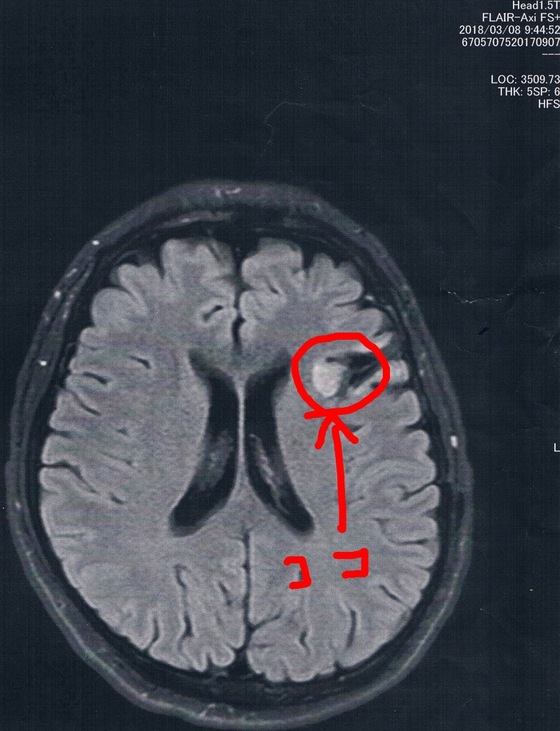

今回2018/3/8(手術後44か月)のMRI画像